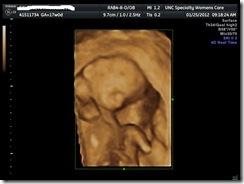

17 week ultrasound

Here are the photos from the 17 week ultrasound!!! Even though he is tiny, I think he is super cute! Smile

How cute is that little tush?!?!?